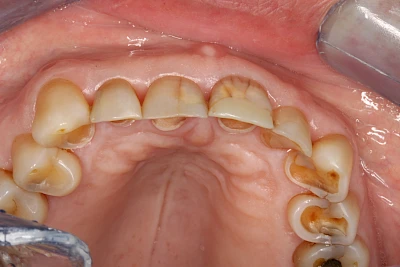

Auswaschung (Erosion) dagegen ist eine Verschleißerscheinung der Zähne aufgrund von immer wiederkehrenden Säureangriffen durch die Nahrung, verstärkt zum Beispiel durch den Genuss säurehaltiger Getränke oder Speisen. Auch bei Menschen mit einer Essstörung (z. B. Bulimie) können die Zähne durch die Magensäure ausgewaschen erscheinen.

Eine Sonderform sind sogenannte keilförmige Defekte im Bereich der Zahnhälse. Hier geht man davon aus, dass Knirschen und Pressen in Kombination mit falschen Putzgewohnheiten (zu hoher Putzdruck, Verwendung von Zahnpasta mit hohen Abrasionswerten) eine Rolle spielen.